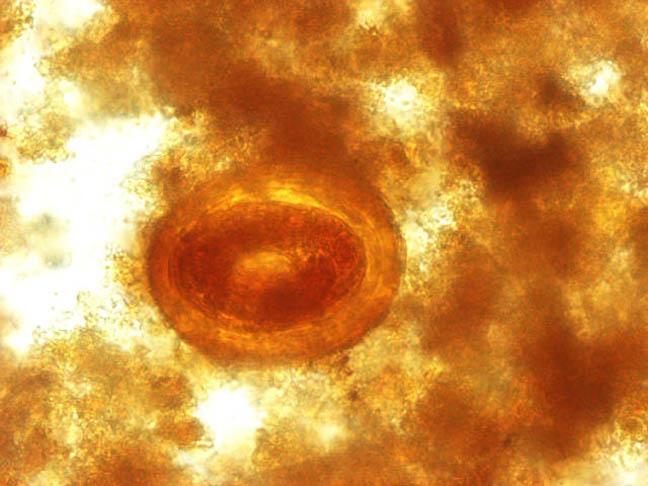

- 40x

Ascaris

Notice the corticated ova